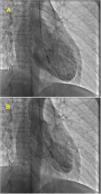

At admission, her heart rate was 105 bpm and blood pressure was 109/74 mmHg. Cardiac and pulmonary auscultation were normal. She denied having chest pain, respiratory distress, palpitations or recent infection. An electrocardiogram (ECG) was performed, revealing a discrete ST-segment elevation (<0.5 mm) in leads II, III, aVF and V2 to V6 and a slightly prolonged corrected QT interval (474 ms) (Figure 1A). The arterial blood gas analysis revealed compensated respiratory alkalosis without hypoxemia and the blood workup showed normal leukocyte count and C-reactive protein, elevated N-terminal brain natriuretic peptide (3300 pg/mL), positive troponin I (1.92 ng/mL, cut-off for myocardial infarction >0.1 ng/mL) and elevated D-dimer (1.2 μg/mL). A CT pulmonary angiogram was also performed but revealed no abnormalities. The echocardiogram showed akinesia of the midventricular and apical segments of all walls and hypercontractile basal segments, resulting in a severely depressed left ventricle ejection fraction (LVEF) (29%) (Figure 2). The right ventricle was undilated with a normal longitudinal function. No relevant valve disease or pericardial effusion were found. The patient was then transferred to the intensive cardiac care unit. The next day, the ECG showed a biphasic T wave in lead V2 and negative T waves in leads I, II, III, aVF, aVL and V3 to V6 (Figure 1B). A coronary angiography was performed and revealed no significant lesions of the epicardial coronary arteries. The ventriculography, however, showed an apical ballooning ventricle with a moderately depressed LVEF (Figure 3).

(A) Electrocardiogram at admission revealing a discrete ST-segment elevation in leads II, III, aVF and V2 to V6 and a slightly elevated corrected QT interval; (B) Electrocardiogram performed one day after admission showing a biphasic T wave in lead V2 and negative T waves in leads I, II, III, aVF, aVL and V3 to V6.